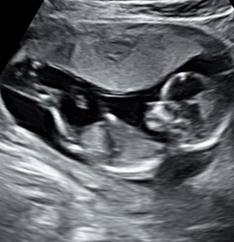

2D Images